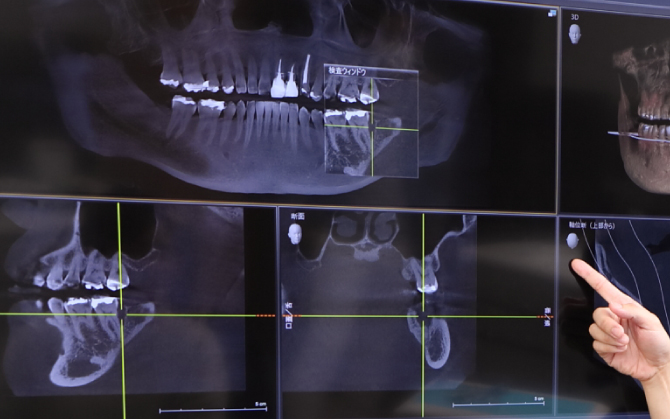

診査・診断・治療計画

診査・診断・治療計画は、オールオン4を成功に導くために必要なとても大事なステップです。

3Dスマイルデザイン、ワックスアップ、ラジオグラフィックガイド等によるプランニングに基づいて、患者様それぞれに合わせたオーダーメイドの治療を慎重に進めていきます。